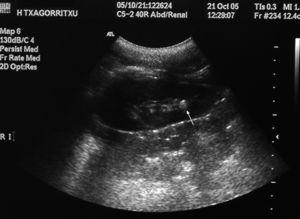

En la ecografía renal, se observaron imágenes con sombra acústica en ambos riñones y en la tomografía computarizada (TC) helicoidal 2 cálculos radioopacos en los grupos caliciales superior e inferior del riñón derecho, y otro más situado en el grupo calicial inferior del riñón izquierdo, excluyéndose la dilatación de la vía urinaria y la presencia de cálculos ureterales (figs. 1 y 2).

Figura 2.TC helicoidal sin contraste intravenoso. Cálculo en grupo calicial inferior del riñón izquierdo (flecha color negro).